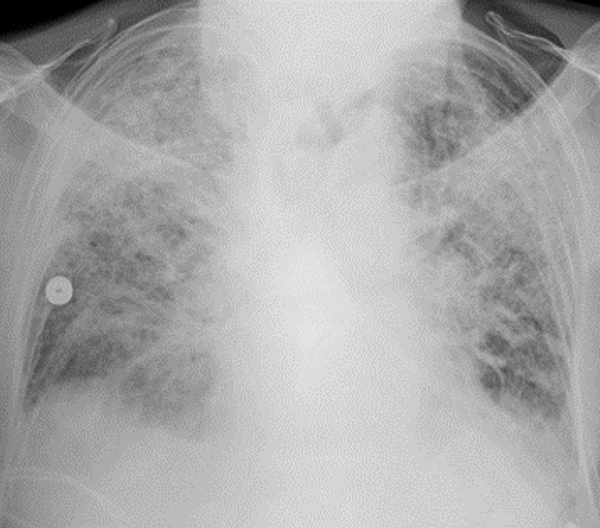

Gebleken is dat als patiënten ernstig ziek worden van COVID-19 dit meestal gebeurt in de tweede week van de besmetting. De koorts neemt progressief toe en vaak ontstaat een ernstige ontstekingsreactie in de longen die hyperinflammatoire shocklong of ARDS – acute respiratory distress syndrome -genoemd wordt. Hierbij treedt lekkage van de longblaasjes, waar de gaswisseling plaatsvindt, op waardoor de ademhaling ernstig bemoeilijkt wordt. Beademen wordt veelal noodzakelijk en organen kunnen uitvallen vanwege een tekort aan zuurstof.